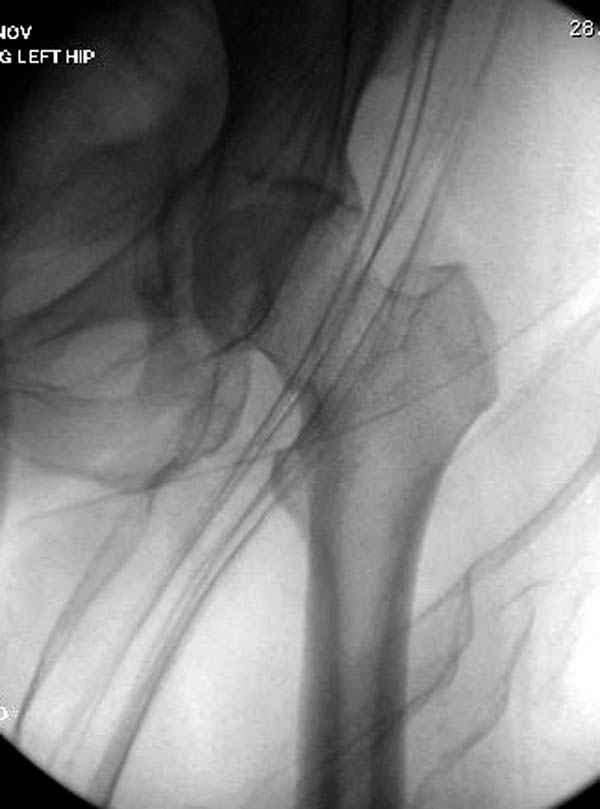

В данный момент скелетное вытяжение поучается через перелом шейки, а фиксированный перелом шейки будет участвовать в процессе вытяжения через каннюлированные шурупы.

Перелом шейки смогли зафиксировать через пару дней, ацетабулум до сих пор не оперирован, на вытяжении.

Из-за упущенного времени (три недели с момента

поступления) ацетабулум ведем консервативно.